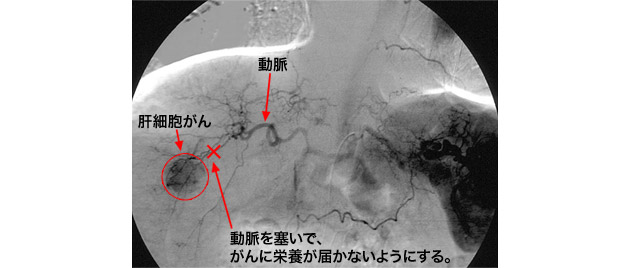

まずは血管造影検査を行います。肝臓の動脈は大動脈から枝分かれして出ていますが、より細かく把握するために、造影剤という薬を動脈の中に注入しながらレントゲン写真を撮ります。

検査では、まず最初に足の付け根の動脈(大腿動脈)周囲に局所麻酔をして、そこから細い管(カテーテル)を肝臓の動脈まで入れていくことから始まります。造影剤を使った血管造影の写真を参考にしてさらにカテーテルを肝臓の動脈の奥まで進めていきます。 目的とするがんのすぐ近くまでカテーテルが挿入できたら、そこから腫瘍を固める薬(リピオドールという油性造影剤と抗がん剤を混ぜたもの)や、腫瘍に栄養を運んでいる動脈を塞いでしまう薬(スポンゼルという止血剤を細かく切ったもの)で塞いでしまいます。つまり、がんに栄養が行かないように「兵糧責め」にしてしまう治療法です。

なぜこのような治療が可能かといいますと、がんと正常の肝臓では血流の流れが異なるからです。肝細胞がんは肝臓の「動脈」から栄養を受けることがほとんどですが、その他の正常な肝臓は動脈からでなく、腸から吸収された物質を血液にのせて肝臓に運ぶ「門脈」という血管で主に栄養されています。したがって、動脈を塞ぐと肝細胞がんは死んでしまいますが、肝臓の正常な部分は門脈に栄養されているためダメージを受けません。